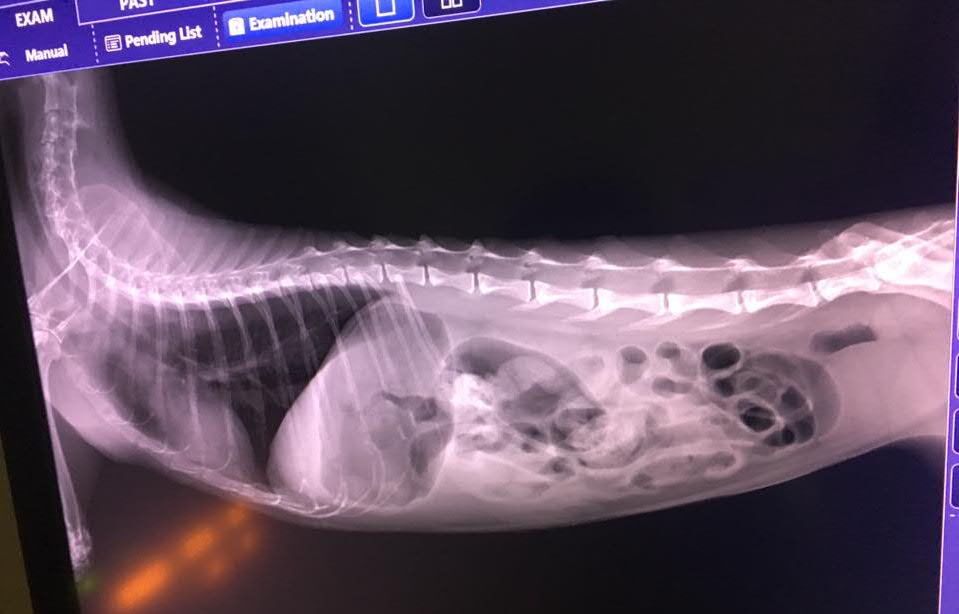

擔心腎臟部分有結石因此做了X光檢查,但胃部脹氣(全空沒食物),且大便多,看不太出來